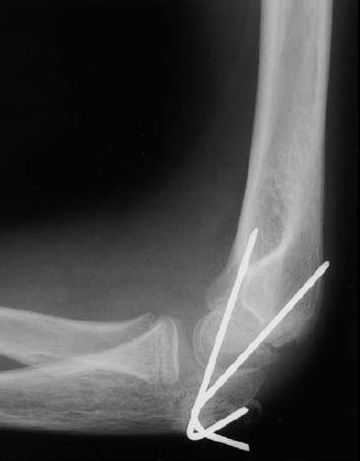

Internal fixation of elbow fracture

This X-ray shows a supracondylar humerus fracture that has been put into the correct position and held in place with two pins. The pins will be removed after healing has begun.

Reproduced from Surgical management of pediatric fractures in the upper extremity, Flynn J, Sarwark J, Waters P, Bae D, Lemke L: Instr Course Lect 2003, 54: 635-645.